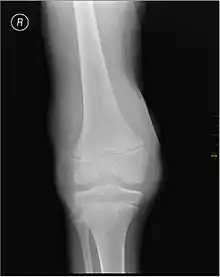

Muscle and joint haemorrhages – or haemarthrosis – are indicative of haemophilia,[7] while digestive tract and cerebral haemorrhages are also germane to other coagulation disorders. Though typically not life-threatening, joint bleeding is one of the most serious symptoms of haemophilia. Repeated bleeds into a joint capsule can cause permanent joint damage and disfigurement resulting in chronic arthritis and disability. Joint damage is not a result of blood in the capsule but rather the healing process. When blood in the joint is broken down by enzymes in the body, the bone in that area is also degraded, this exerts a lot of pain upon the person affected by the disease.